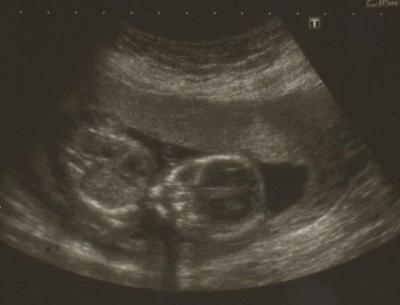

Ich war ja Am dienstag beim Frauenarzt .. kurz zur erinnerung... : Ca. 120 gramm und 13,3 cm groß ;) Das bild ist also von 15+6 sprich vom Letzten tag der Woche 16 ;-) Seit mittwoch bin ich dann in die 17te ssw. gekugelt. hier das bild unserer kleinen Peanut ;-) ES hat sich ja noch nicht gezeigt .. also bleibts ne erdnuss erstmal ;)) haha

Oh man... man erkennt echt immer mehr...Köpfchen, Oberkörper ....

Ohhhh wie süß - Waaaahnsinn wie groß das Buzi schon ist